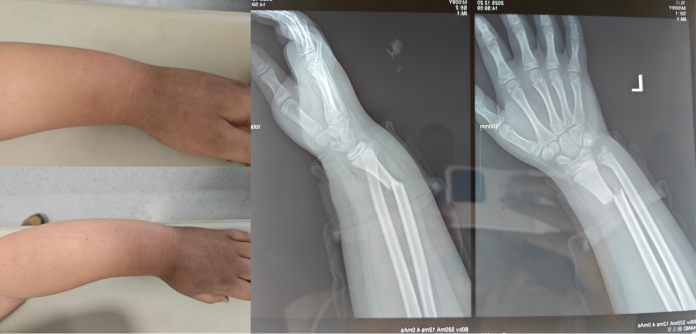

阳光讯(记者 郑亚雷 通讯员 曾雪琴)“医生,孩子才9岁,我们真的不想让他做手术!”近日,西安市红会医院手法复位室门口,家长带着哭腔的恳求,牵动着在场医护的心。据了解,4天前,男孩明明(化名)户外玩耍时不慎摔倒,左手撑地导致左腕剧痛、肿胀变形,无法屈伸。当地医院检查显示其左侧尺骨、桡骨远端双骨折,合并下尺桡关节脱位,建议手术切开复位固定。心疼孩子的家人辗转得知红会医院手法复位技术精湛,尤其擅长儿童骨折保守治疗,于是毅然赶往西安市红会医院。

接诊医生杜龙龙检查发现患儿腕部畸形明显、肿胀严重,影像提示骨折脱位情况复杂,复位难度较大。他立即上报董博主任与周健副主任医师。两位专家迅速到场,共同研判病情,董博主任明确治疗方向,周健副主任医师补充复位要点,三人快速敲定个性化方案,耐心告知家属风险与注意事项后,家属签字同意。

复位操作中,在董博主任与周健副主任医师的指导下,杜龙龙医生先对患儿左腕轻柔持续牵引,缓解骨折嵌顿,再顺着骨骼生理结构精准推挤移位骨端,同步复位脱位关节。董博主任在一旁紧盯患儿的肢体反应,不时提醒:“力道再轻一点,注意观察指尖血运。”周健副主任医师则密切关注骨骼复位的角度,及时给出调整建议。短短几分钟后,随着轻微骨擦音,男孩畸形的腕部逐渐恢复正常。后续石膏固定及复查X线片显示,骨折断端对位对线良好,脱位完全纠正,复位效果超预期。